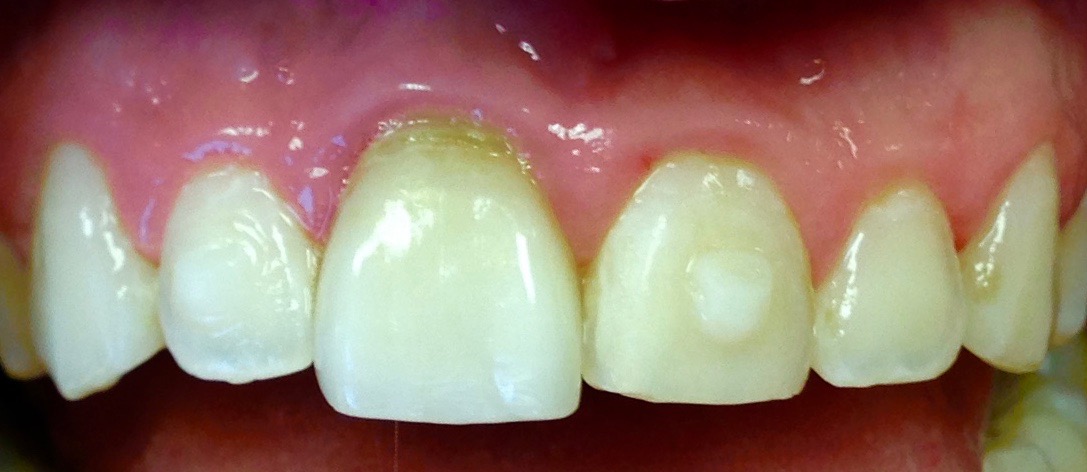

Digital technology is not only great for diagnosis and treatment planning, it also allows that plan to be easily integrated into the restorative workflow. This is a distinct advantage over conventional workflows, especially in esthetic cases when it is critical to meet patient expectations. An illustration of this is a patient presenting with a desire to address his chipped maxillary incisors to make them more esthetic (Figure 1). Using digital photography, a retracted photograph of the patient's teeth was imported into smile-design software, which provided a quick and simple means of establishing a symmetrical restorative design for the patient (Figure 2). Within the same software, the proposed restorations were then overlaid on a full-face smiling photograph (Figure 3), and the patient was able to compare before-and-after photographs (Figure 4). The patient approved of the proposal, which was then imported into CAD software to facilitate fabrication of the final restorations based on the smile-design proposal (Figure 5).

Fig 1. Retracted preoperative view of chipped maxillary incisors.

Figure 1